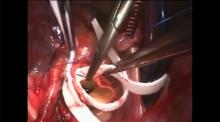

This video commences with a brief presentation on the management of Type A aortic dissections and proceeds into an operative video showing the steps used when operating on these cases.